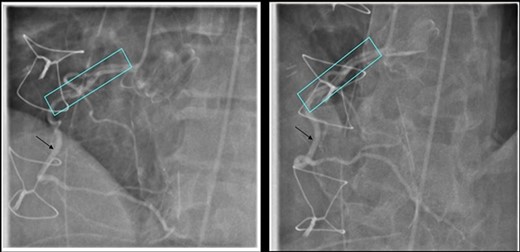

He underwent a successful urgent mechanical aortic valve replacement (25 mm On-X mechanical valve) on cardiopulmonary bypass (CPB) with cardioplegic arrest. Cardioplegic protection was achieved using antegrade intermittent cold blood. Intra-operatively, a severely calcified functional bicuspid aortic valve with commissural fusion between the right and left cusps was seen. The aortic tissue was noted to be fragile. At the end of the procedure he developed atrial fibrillation which reverted to sinus tachycardia on administration of Amiodarone. His aortic cross clamp time was 91 min and bypass time was 116 min. He was successfully weaned off CPB and safely transferred to the intensive care unit (ITU). On arrival to the ITU, he went into refractory VF requiring 12 attempts of electrical cardioversion, amiodarone infusion and lidocaine, with a blood gas lactate of 5.3. His ECG revealed inferior and lateral ST depression and TOE showed inferior wall hypokinesia. An emergency coronary angiogram revealed an extensive right coronary artery (RCA) dissection extending from the ostium to the mid-vessel as the cause of VF (Fig. 2).

Coronary Angiogram showing RCA dissection extending from ostium to mid-vessel (box), normal coronary artery (arrow).